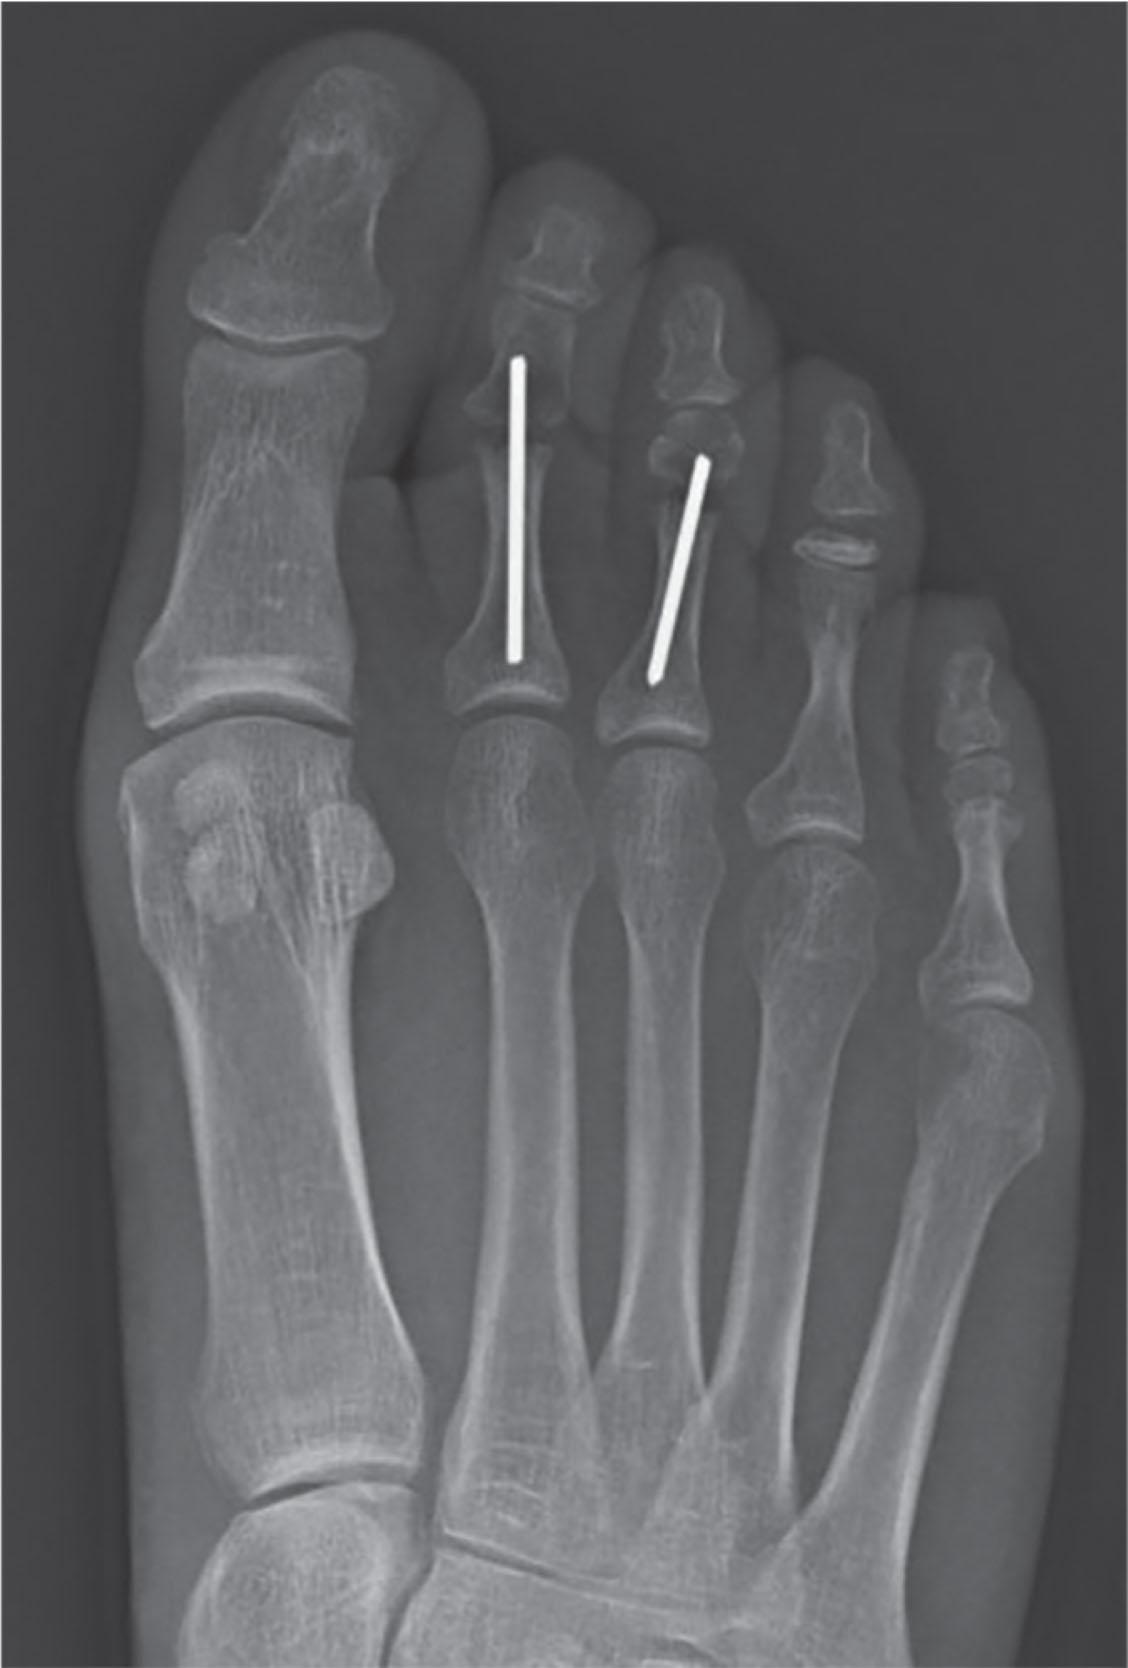

Intramedullary fixation for hammer toe correction has been advocated in an effort to secure permanent fixation without the use of Kirschner wires. Absorbable implants, screw fixation ( Figs. 9-41 and 9-42 ), wire loops, and other permanent intramedullary devices ( Fig. 9-43 ) have all been reported.

Fig. 9-43, Examples of intramedullary fixation for hammer toe repairs. A , Stayfuse (Tornier, Minneapolis, Minn.), with correction of deformity. B , Ipp-On (Integra, Plainsboro, N.J.), with correction of deformity. C , Pro-Toe (Wright Medical, Memphis, Tenn.), D , Example of implant failure with persistent pain. E , Smart Toe (Stryker, Kalamazoo, Mich.), with extra Kirschner wire fixation. F , Smart Toe implant 4 years post op with fracture of implant but patient is asymptomatic